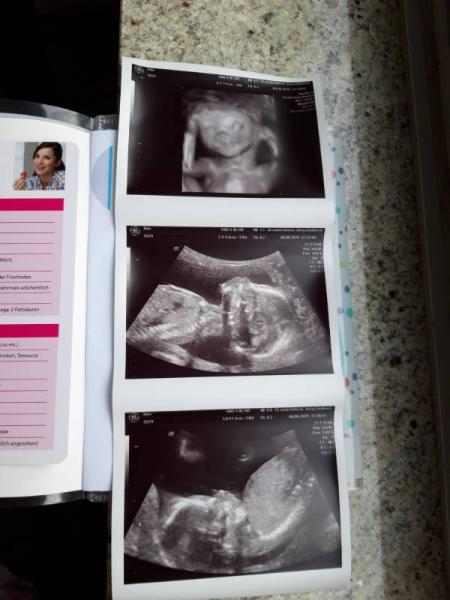

Waren heute bei 17+6 bei unserer Untersuchung. Unser Mäuschen wird zu 70% ein Mädchen. Und alle Organe sind am richtigen Ort und alle Körperteile sind vorhanden und super entwickelt Wir sind sehr glücklich

Bild zu Zurück vom Ultraschall - Forum für Januar - Mamis

Wow, das sind ja beeindruckende Bilder!! Wunderschön! Schön, dass euer Krümelchen so gut entwickelt ist Hauptsache gesund, da ist das Geschlecht ja Nebensache.

Tolle Bilder